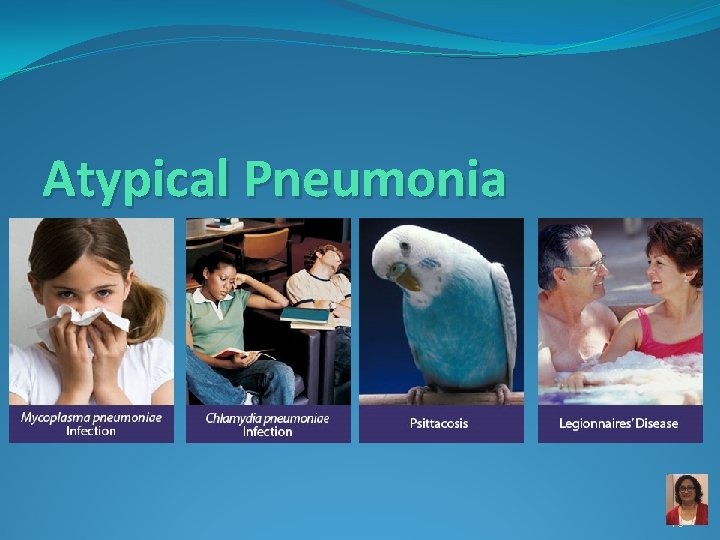

Atypical Pneumonia 76

Mycoplasma pneumoniae Legionella pneumophila Chlamydophila pneumoniae